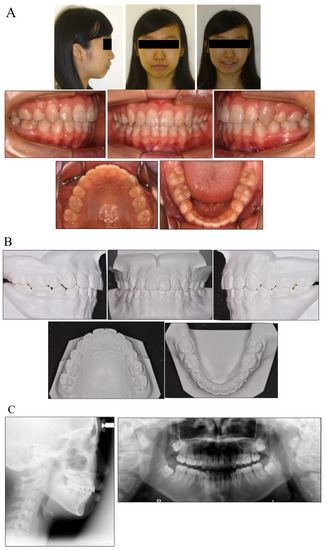

During the active treatment, at three years and six months after debonding, no significant periodontal problems, such as gingival recession or loss of tooth vitality, were observed. Panoramic radiographs before and after treatment showed no significant reduction in the crest bone height and a slight root resorption (Figure 4).

Figure 4.

Facial and intraoral photograph (A), dental casts (B) and radiographs ((C) lateral cephalogram; panoramic radiograph) of post-treatment at three years and six months (patient is 20 years old).